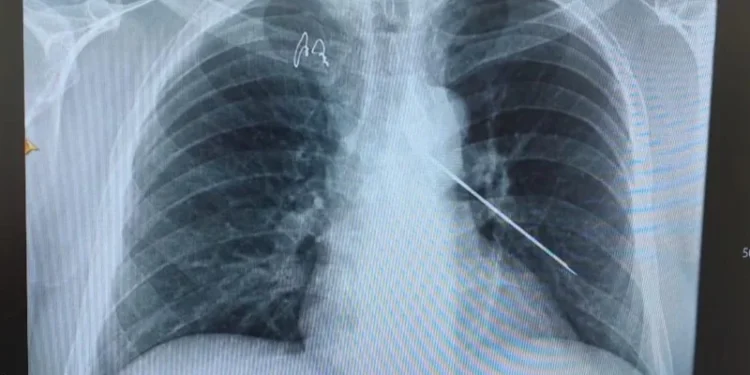

— Мамандар зерттей келе оның денесінде ұзындығы 10 сантиметрге жететін сым барын анықтады. Науқасқа бұған дейін басқа ауруханада ота жасалып, оң жақ бұғана сүйегінің сынығына байланысты металл конструкция орнатылған. Сол кейін жылжып кетіп, жанына батып жүріпті. Кезекті ота кезінде мамандар жансыз затты алып тастады. Ота сәтті өтті. Науқастың жағдайы жақсы. Толық ем қабылдаған соң үйіне шығарылады. Белгілі бір уақытқа дейін емхана бақылауында болады, — деді аурухананың баспасөз қызметінің маманы Гүлбану Мақажан.